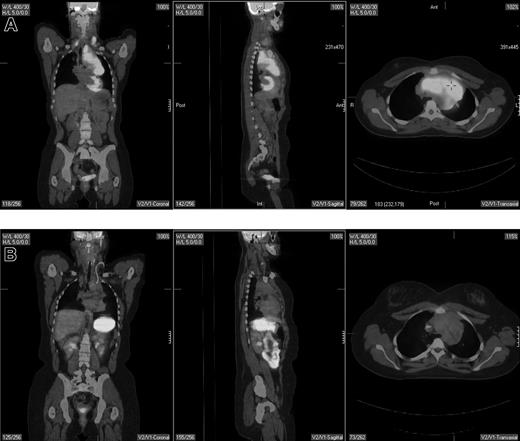

Pretreatment staging determines the extent of disease and helps direct therapy. The Ann Arbor system was initially developed to distinguish patients who might be candidates for radiation therapy from those who would benefit from systemic treatment.29 Traditionally, the Ann Arbor staging system was based on physical examination and bone marrow evaluation but, more recently, CT scans have been incorporated. PET may provide complementary information to conventional staging methods, such as dedicated intravenous contrast-enhanced CT (CECT) and bone marrow biopsy. PET is highly sensitive in detecting nodal and extranodal involvement by most histologic subtypes of lymphoma prior to and following treatment (Figure 1).2,3,20,30-43 Most common types of lymphoma (eg, diffuse large B-cell NHL, follicular NHL, mantle cell NHL, HL) are routinely FDG avid with a sensitivity that exceeds 80% and a specificity of about 90%, which is superior to CT.2,3,33

A pretreatment PET/CT scan in a 48-year-old female patient with Burkitt lymphoma showing widespread nodal and extranodal disease including periaortic, iliac, and mediastinal lymphadenopathy in addition to extensive involvement of the bone/bone marrow, both thyroid lobes and focal liver involvement.

PET and CT are concordant in staging 80% to 90% of patients with diffuse large B-cell lymphoma, follicular lymphoma, and probably also mantle cell lymphoma.33,35 In the 10% to 20% of patients in whom a discordance is observed, PET typically results in upstaging due to the additional presumed sites of disease detected by PET alone such as lymph nodes of 1 cm or smaller in short axis by CT and splenic and hepatic infiltration. In contrast, concordance of PET and CT in determining clinical stage occurs in only about 60% to 80% of patients with HL. Discordant findings occur with a comparable frequency (eg, 10%-20%) in both directions.34,37-42 Although most studies show that PET-negative/CT-positive findings are less common than the converse, it is clear that PET alone cannot replace CT for pretreatment staging of HL.34,37,39,41

PET can detect focal or multifocal bone/bone marrow involvement in lymphoma patients with a negative iliac crest bone marrow biopsy, subsequently confirmed by histopathology or magnetic resonance imaging (MRI)44-46 However, PET alone is unreliable in detecting bone marrow involvement, particularly of limited extent (ie, ≤ 10%-20% of marrow space); estimates of PET sensitivity for detecting marrow infiltration in NHL and HL based on a recently reported meta-analysis were 43% (95% CI, 28-60) and 76% (95% CI, 47-92), respectively.46 While PET may also detect extensive diffuse bone/bone marrow involvement, these patients typically have a positive bone marrow biopsy. Moreover, diffusely increased bone marrow uptake on PET may be due to reactive myeloid hyperplasia, and, therefore, such uptake should be interpreted with caution.45 PET-positive bone/bone marrow findings should be confirmed by biopsy or MRI if a change in treatment is planned based on these findings. Thus, PET cannot substitute for bone marrow biopsy in lymphoma staging.